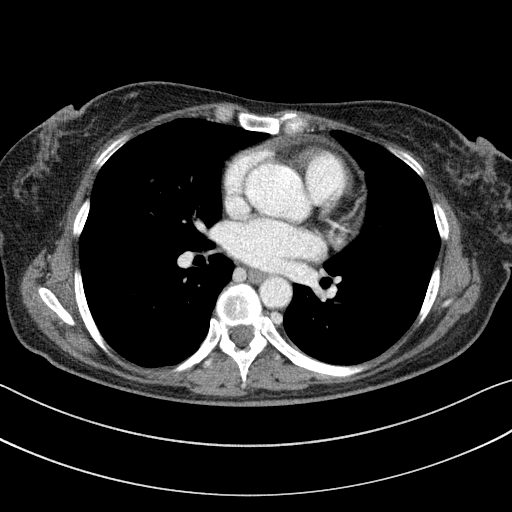

Image Grid

4×3 grid: Rows show different image types (Original NATIVE, Reconstructed NATIVE, Original VENOUS, Generated VENOUS), Columns show windowing techniques (No Window, Lung Window, Mediastinum Window)

Original NATIVE CT scan (input)

Mediastinum window (WL 40, WW 400 → Low −160, High +240)

Reconstructed NATIVE CT scan (cycle consistency)

Mediastinum window (WL 40, WW 400 → Low −160, High +240)

Original VENOUS CT scan

Mediastinum window (WL 40, WW 400 → Low −160, High +240)

Generated VENOUS CT scan (A→B translation)

Mediastinum window (WL 40, WW 400 → Low −160, High +240)

Windowing Parameters

- Mediastinum Window: WL 40, WW 400 → Low −160, High +240 (optimal for soft tissues)